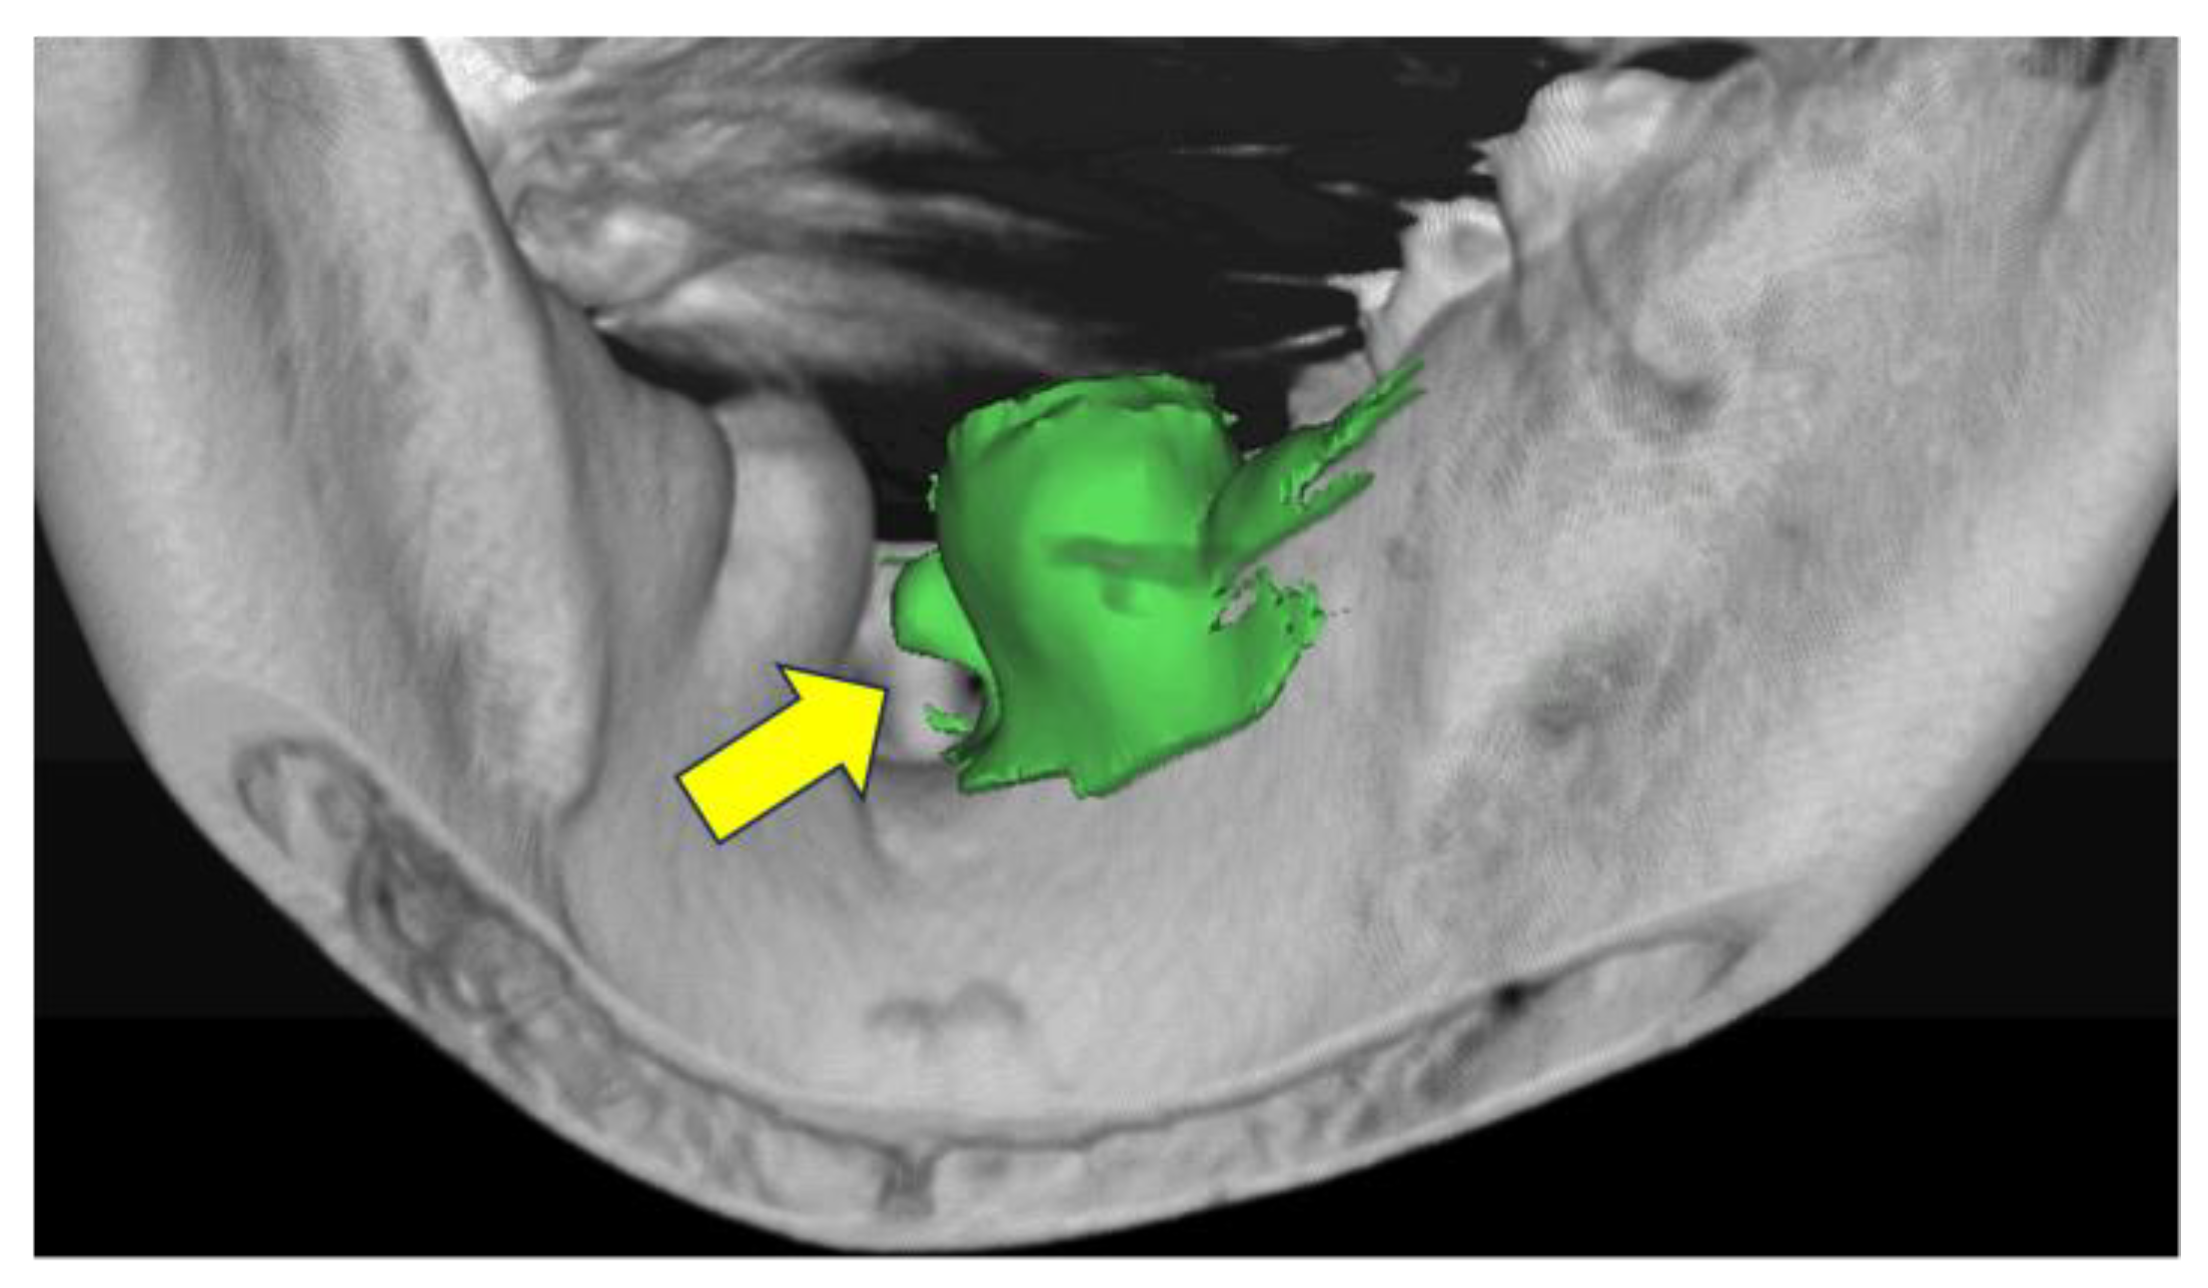

Data were obtained from patients who underwent plain mandibular computed tomography (CT) at the Department of Radiology, Fukuoka Dental College Hospital between April 1, 2015, to March 31, 2020. A total of 2,158 people were eligible, with 147 randomly selected from the teenage group, which had the lowest number of patients. An equal number of 147 individuals were selected from each of the other age groups to ensure a consistent sample size across all age groups. Those aged 80 years were placed in a separated group, and a total of 1,176 people were surveyed. Medical records and CT images from our hospital were used for the survey. To identify and evaluate the mandibular tori, clinical evaluations based on intraoral findings by physicians and radiographic interpretation reports by radiology technicians were performed. The survey contents included age at the time of CT imaging, sex, presence or absence of a mandibular torus, and detailed information on the mandibular torus (site of occurrence, thickness, shape, volume, and bone density). Detailed information on the mandibular ridge was obtained by converting the files into three-dimensional CT images using SIMPLANT® (Dentsply Sirona) (Figure 1). Patients who underwent CT were included if the imaging was conducted to (1) obtain accurate diagnoses before implant placement surgery, (2) understand the positional relationship between the impacted mandibular wisdom teeth and the mandibular canal, (3) diagnose residual apical tooth lesions and cysts, and/or (4) identify the presence and extent of fracture lines at the time of trauma. The subjects were patients who underwent plain CT imaging of the mandible to diagnose pathological conditions that did not cause major anatomical changes and to formulate treatment plans. The following participants were excluded: 1) those whose continuity of normal cortical bone was lost due to trauma, tumors, or tumorous bone swelling; 2) those with a history of surgical jawbone reshaping and tumor resection; 3) those who refused to participate in the study; and/or 4) those judged unsuitable as research subjects.

Figure 1. Identification and analysis of mandibular tori using computed tomography analysis software. The arrow points to the identified mandibular tori. This allows for the evaluation of morphology, size, bone density, etc., at specific locations.